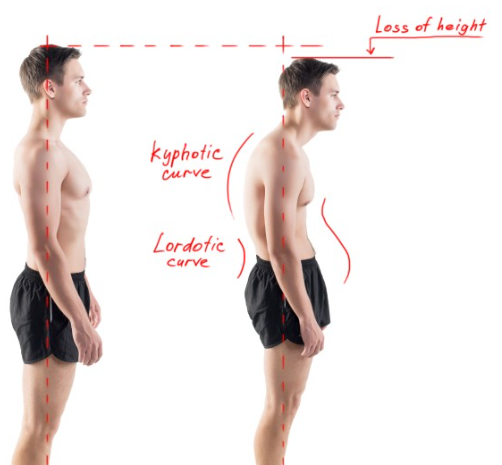

골격의 정렬 이상 또는 뼈의 외상

흉추가 과도하게 굽어있는 굽은등 상태인 후만상태(Excessive thoracic kyphosis)이거나 거북목(Increased cervical lordosis)인 경우에 견갑골문제가 발생할 수 있습니다.

후만과 거북목으로 인해 견갑골이 앞으로 빠지는 전인상태(Scapular protraction)이 되면서 견봉하공간이 좁아지면서 어깨 충돌가능성이 증가할 수 있습니다.

굽은등, 거북목 -> 견갑골 전인상태 -> 견봉하공간 좁아짐 -> 충돌 증가

환자의 경부, 흉부의 해부학적 자세 시 흉추의 Kyphosis, 경추의 거북목, 측만, 견갑골의 대칭성 확인

흉추의 과후만을 교정해주는것이 재활초기에 매우 중요합니다. 여러가지 스트레칭도 중요하지만 평소 바른자세도 지속적으로 시행해주어야합니다.